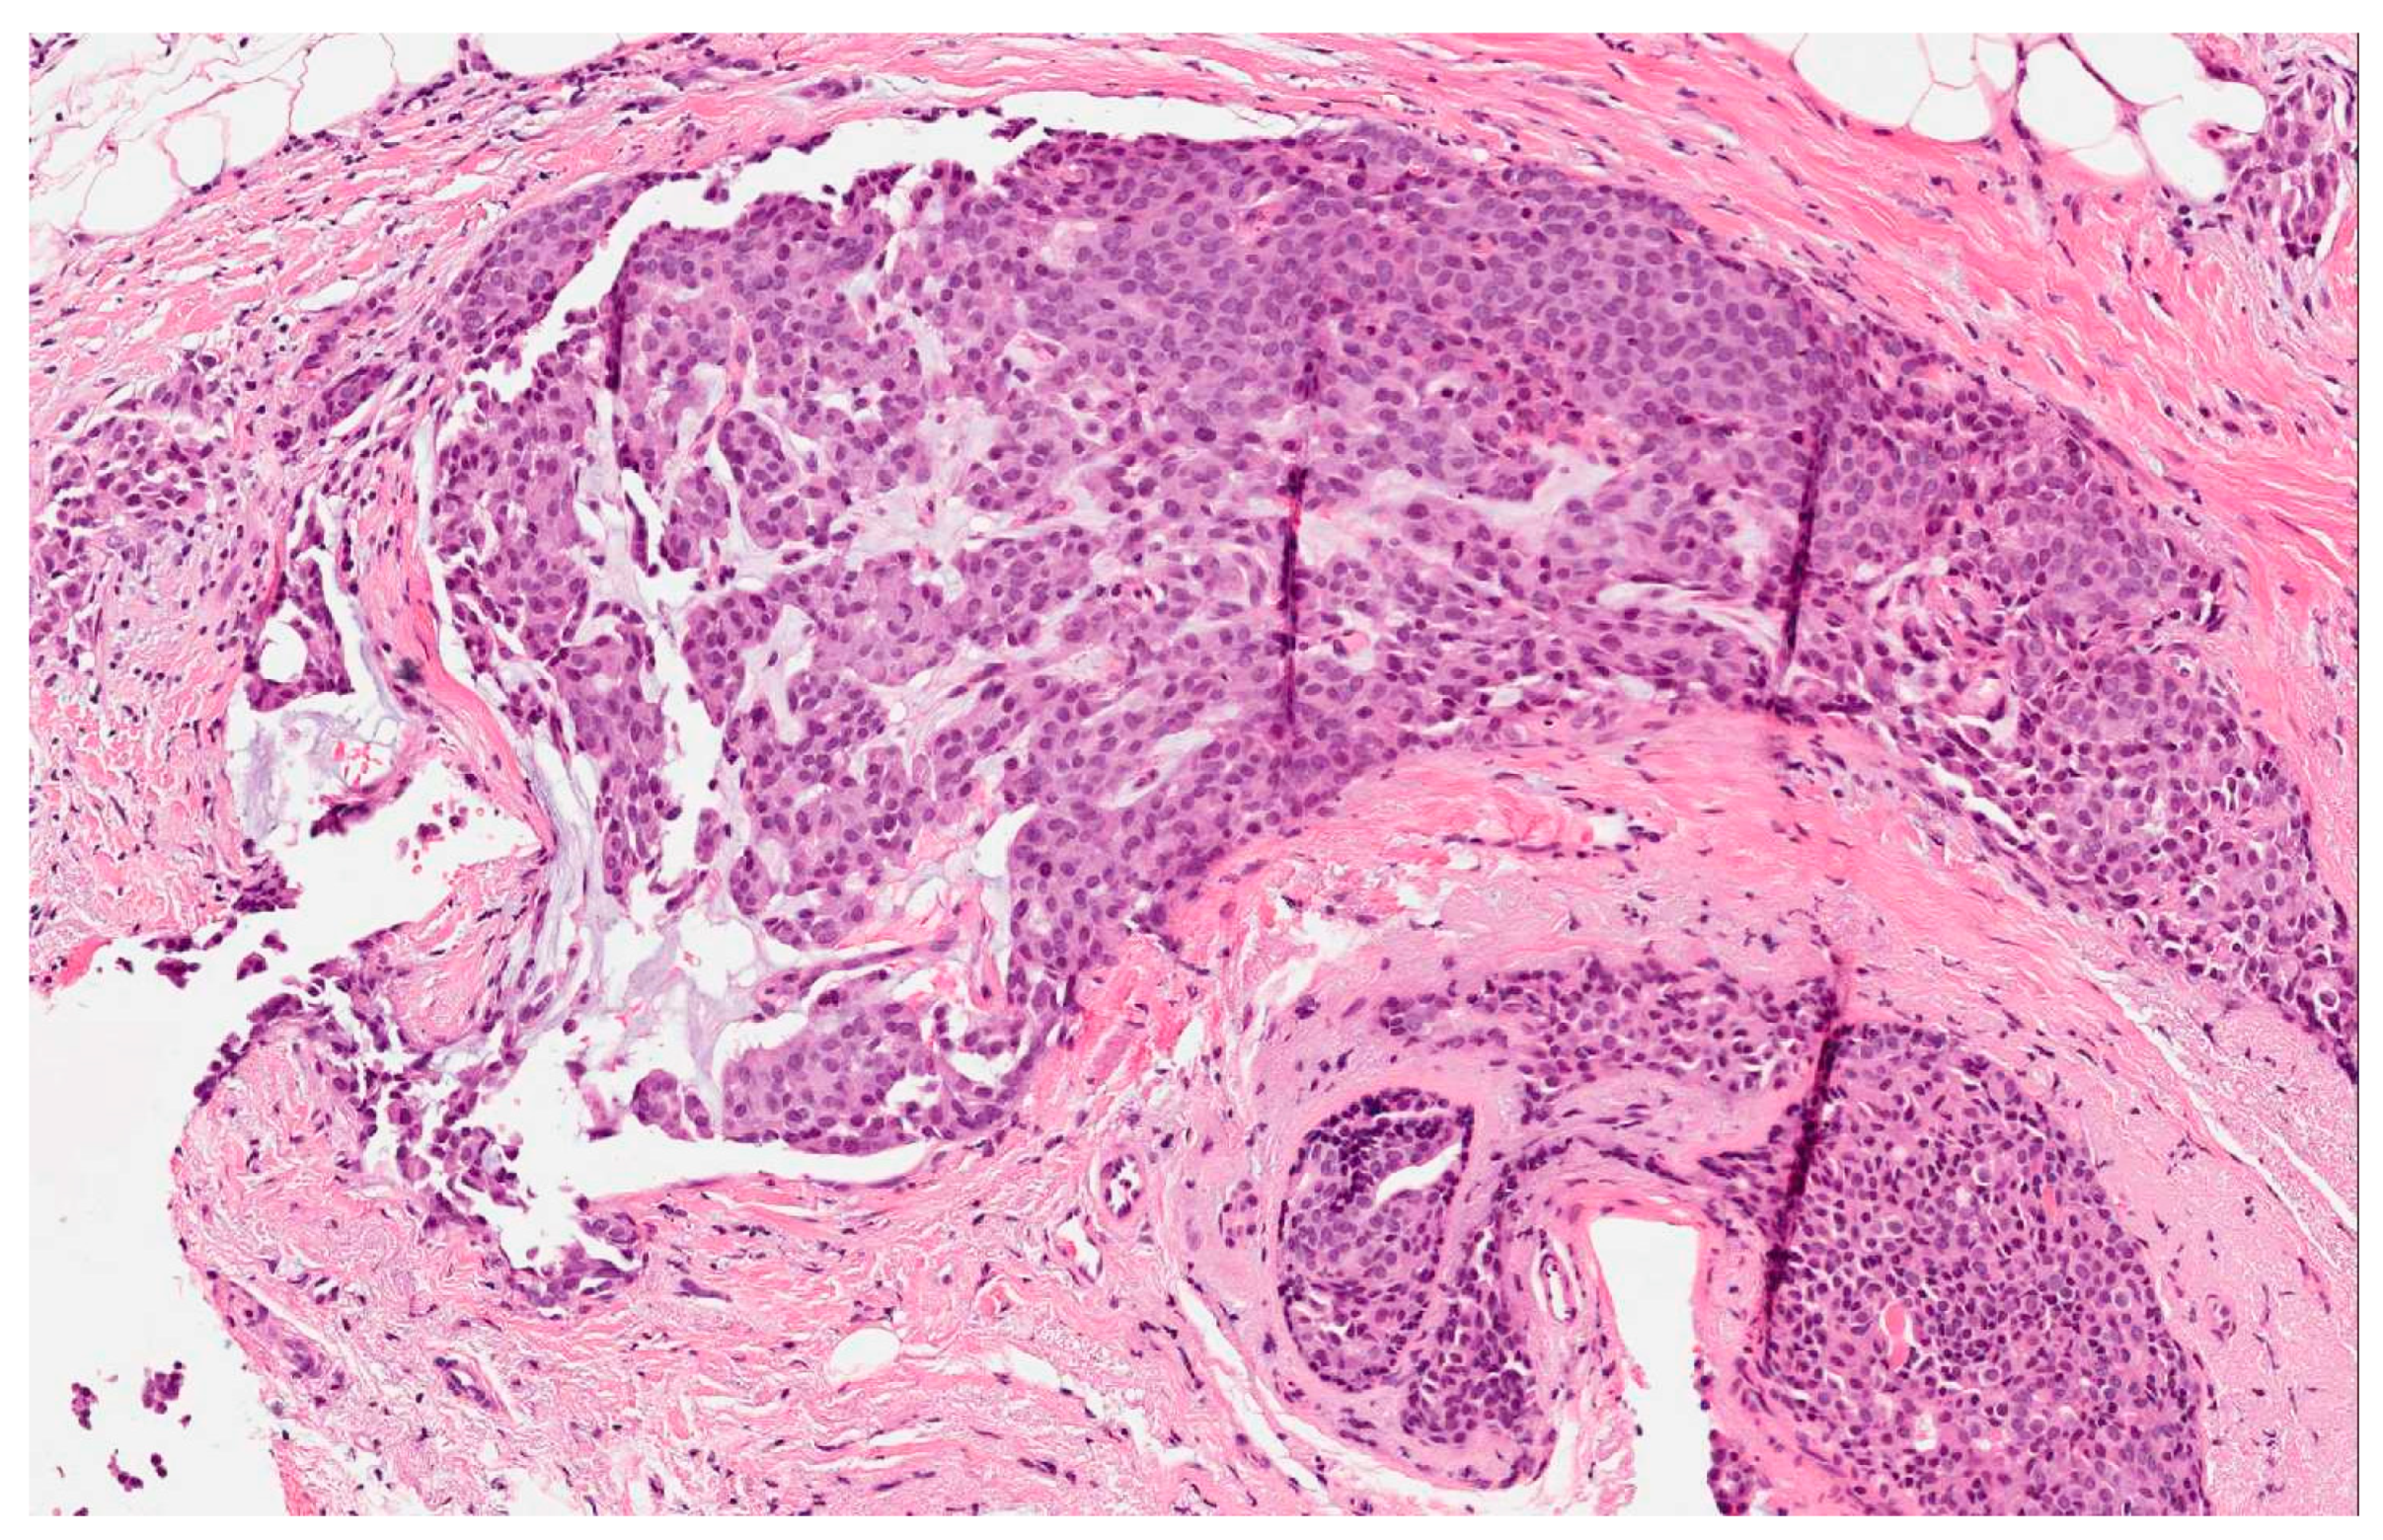

- The presence of over 50% of neoplastic cells expressing neuroendocrine markers of immunohistochemistry such as chromogranin A and synaptophysin (Figure 2). Neuron-specific enolase (NSE) and CD56 appear to result in lower sensitivity and specificity, mostly because they are normally present in breast tissue [2,5,6,11]. When the neuroendocrine characteristics are shown in less than 50% of cancer cells, the tumor should be identified as a breast cancer with neuroendocrine differentiation. The focal neuroendocrine differentiation within the carcinoma of the breast is common and has no prognostic significance.